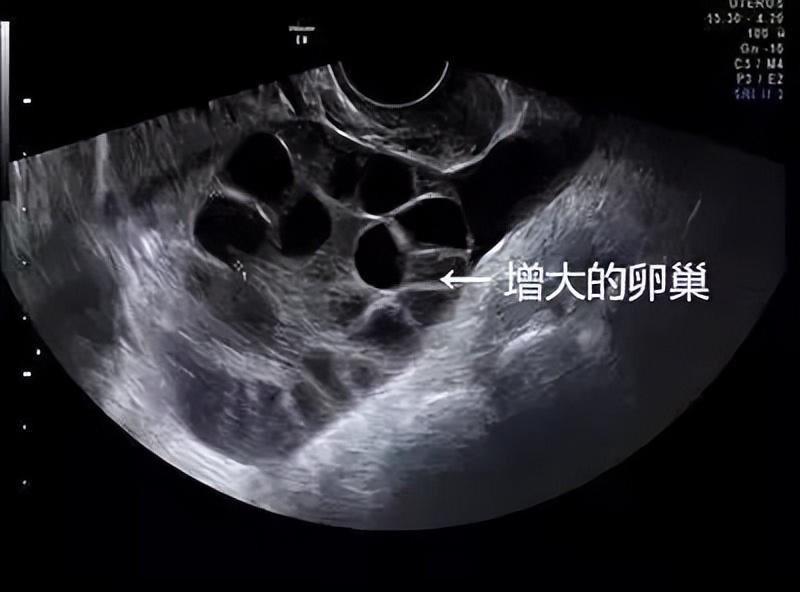

女性的卵子都是月经前定期排放的,数量很少,使用这种排卵针虽说会在短期内增加卵子的排放量,但对身体造成的损伤却也是不可逆转的,很容易造成卵巢增大、排卵失常的情况,双卵、多卵也是常有的事情。

“卵巢异常增大”,让有多年从医经历的胡医生忍不住皱起眉头,女孩得的病属于“卵巢过度刺激综合征”,一般多发生在注射过排卵针的病人身上。

卵巢增大、提前衰老,严重一点还会导致不孕不育,这对身体造成的损害是不可逆转的。

通过外力促进排卵,会对卵巢造成刺激,女性的生理器官非常敏感,稍有不慎就会造成损害。 一次性取走二十颗卵子,是正常排卵量的几十倍,会导致人的身体器官提前进入衰老期 ,这也说明了卵细胞的重要性。